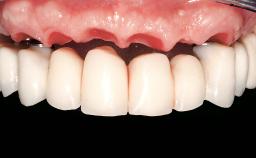

Immediate Loading of Eight Implants in the Maxilla and Six Implants in the Mandible and Final Restoration with Three-Unit and Four-Unit FDPs

Extensive scientific evidence has confirmed that immediately loaded implants with fixed full-arch provisional restorations can osseointegrate with success rates similar to conventionally or delayed loaded implants. A number of immediate-provisionalization techniques for edentulous jaws have been described. Some protocols differ when it comes to prefabricated provisional templates versus complete denture conversion; intrasurgical impressions versus direct relining; and cemented versus screw-retained provisional restorations. In this context, complete-denture conversion has been proposed for either intrasurgical impressions or direct relining. Another possibility is the utilization of a prefabricated provisional to be adapted either in the mouth (by direct relining) or in the laboratory (on a working model obtained from an intrasurgical impression).

Prosthesis Type FDP

SAC Level Complex

Defining Characteristics Fully edentulous upper jaw to be rehabilitated with an implant-borne fixed dental prosthesis

Esthetic Risk High